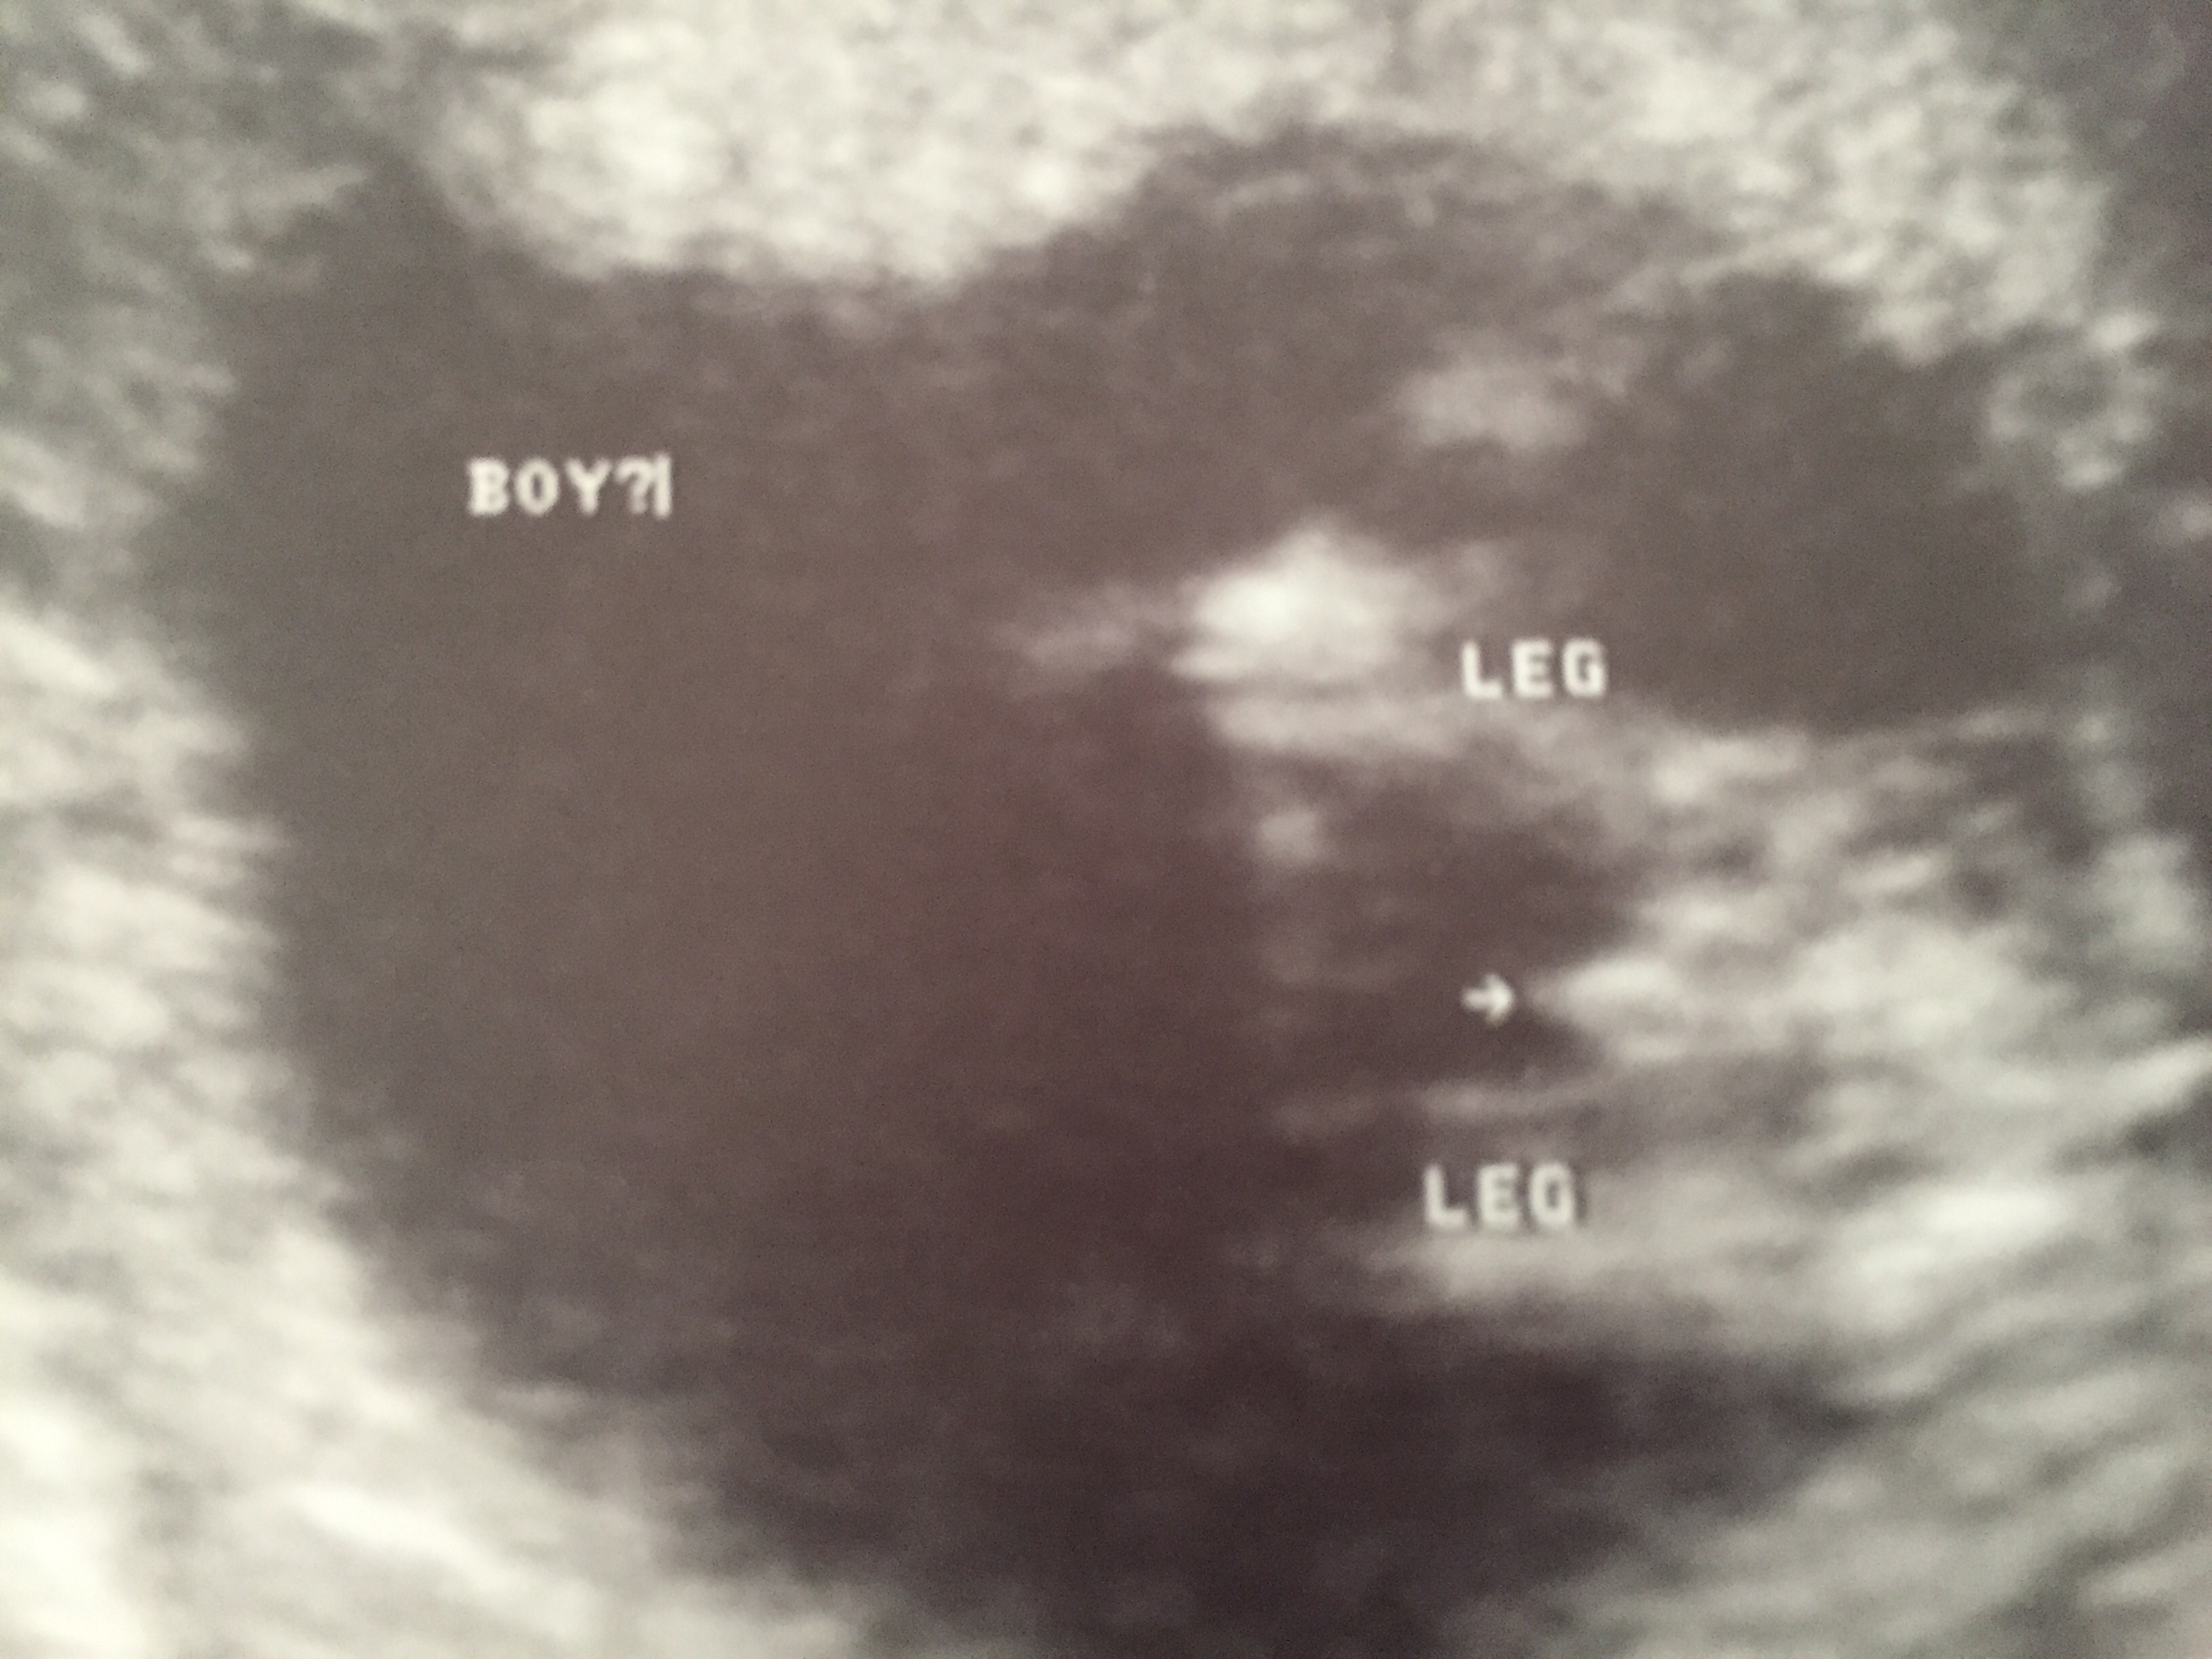

Any chance of girl?? 13w6d potty shot

This is my first post here. I have two boys and would love a girl (especially since my only girl was stillborn at the beginning of the year). I had an early US and tech thought it looked like a boy but said it was still early.

This was 13w6d. Please, is there any chance of this becoming a girl??? I've read others stories and know it can be ambiguous early. Is there any hope? Thank you!Attachment 26557Attachment 26558Attachment 26559Attachment 26557Attachment 26558Attachment 26559